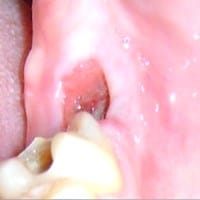

Hace unos días me extrajeron una muela y me quedo un hoyo profundo, allí se me está acumulando comida, ¿Qué hago?